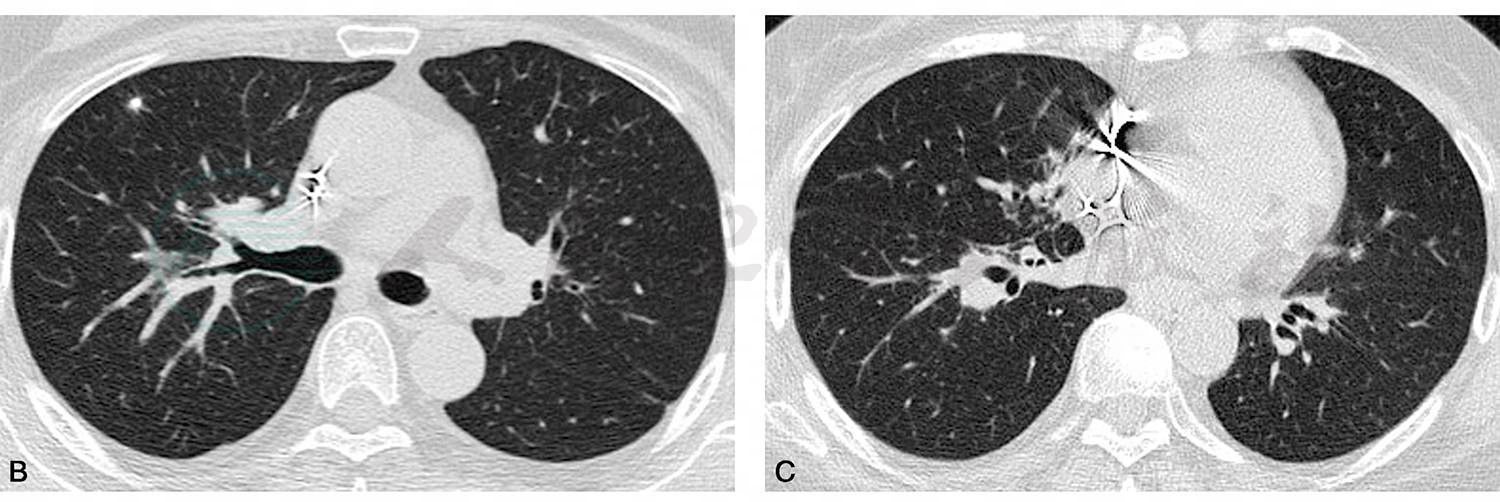

复查胸部薄层CT扫描(2018-08-04):双肺多发微小结节灶,沿支气管血管束分布,考虑结节病(图2)。

图2 胸部薄层CT平扫

A.气管旁淋巴结较前增大;B,C.沿双侧肺门向外周延伸的中央间质增生,沿支气管血管束分布的细小结节影,由肺门向外周分布逐渐稀少(白箭),右肺上叶前段可见较大结节影(白箭头)